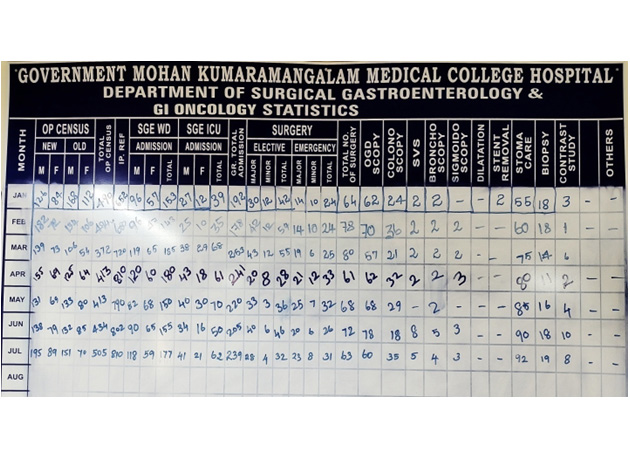

Census:

During the COVID years 2020 and 2021, the performance of our SGE Department was highest in entire state of Tamilnadu under the CMCHIS scheme. Also, we have always been one among the Top two highest performing SGE departments in the entire state under the CMCHIS scheme.

| S. No. | Year | Total OP Census | Total Ward Census | Elective Surgeries | Emergency Surgeries | OGD Scopy | Colono Scopy | SVS | Broncho Scopy | Sigmoid Scopy |

|---|---|---|---|---|---|---|---|---|---|---|

| 1. | 2018 | 4678 | 727 | 498 | 156 | 364 | 162 | |||

| 2. | 2019 | 9443 | 864 | 503 | 163 | 452 | 195 | |||

| 3. | 2020 | 6012 | 601 | 328 | 285 | 206 | 94 | |||

| 4. | 2021 | 6460 | 1296 | 332 | 300 | 532 | 195 | 14 | 10 | 4 |

| 5. | 2022 | 5690 | 1925 | 449 | 210 | 526 | 239 | 47 | 21 | 4 |

| 6. | 2023 (Until July) | 3121 | 1142 | 293 | 195 | 457 | 195 | 21 | 19 | 13 |